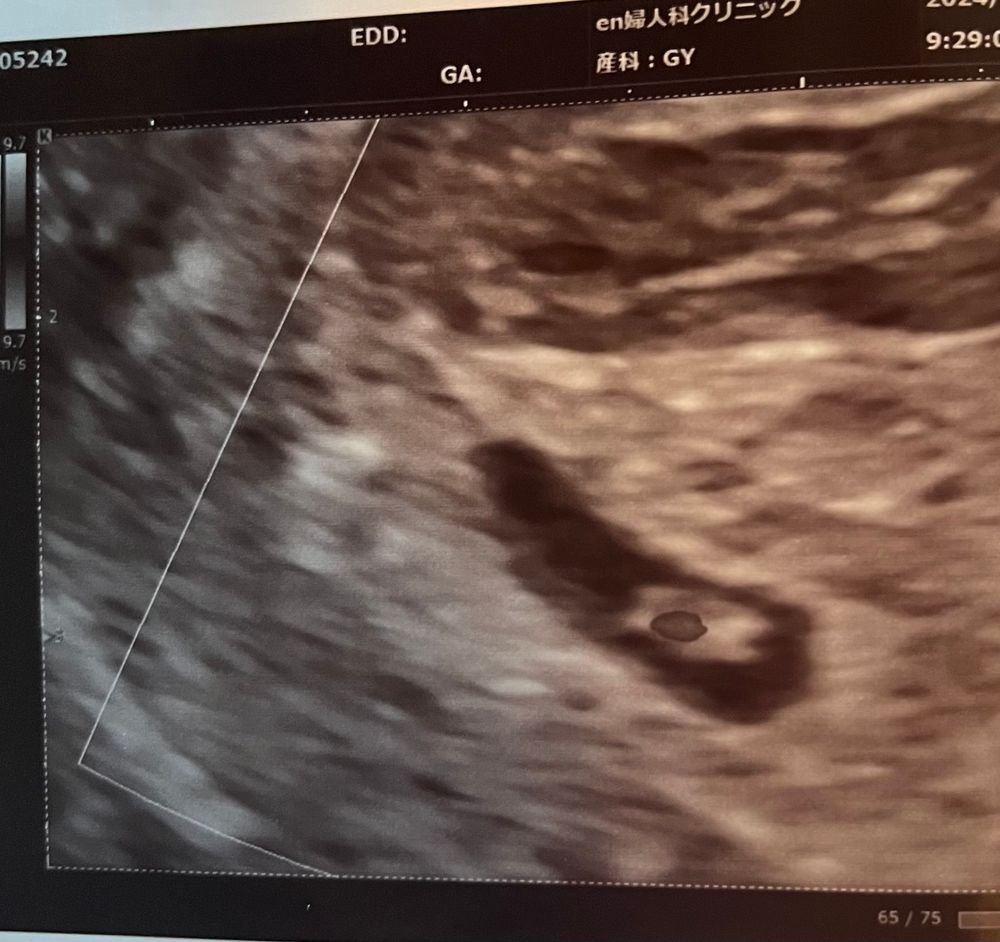

Вопрос знатокам, что кровит? 25 дпп

Ксения, у меня вообще не мажет, только алой кровью льет по 2-4 чайной ложке. Поэтому я сильно тревогу била. Врач не сказала, что именно кровит, вот и пытаюсь понять по снимку узи🤔.

29.03.2024